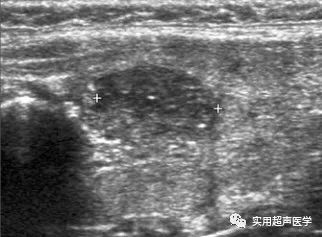

患者,女,45岁,桥本甲状腺炎和并甲状腺乳头状癌(FNA)。左侧叶探及实性低回声结节(游标)伴有内部微钙化。